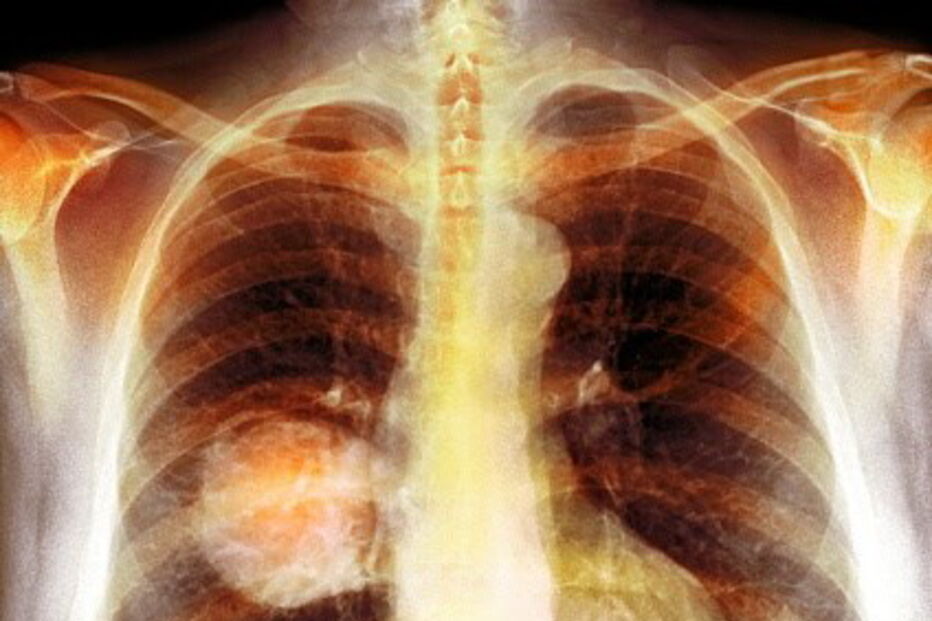

Cancro do pulmão é o que mais mata em Portugal.

O relatório do Programa Nacional para as Doenças Oncológicas 2017, que compila dados entre 2011 e 2015, mostra que a incidência das doenças oncológicas regista um aumento de 3% por ano e é considerada a segunda causa de morte, depois das doenças cérebro-cardiovasculares. Entre os cancros que mais matam está o do pulmão, com um "aumento significativo" nas mulheres.

Ainda segundo o relatório, a seguir ao cancro do pulmão, os do cólon e do reto são os que mais pessoas matam em Portugal. A faixa etária com maior incidência de casos é a partir dos 60 anos.

Nuno Miranda – Continua a ser o do pulmão, com mais de 4 mil óbitos em 2015. Houve um aumento significativo de incidência no sexo feminino. No entanto, sabemos que é um cancro evitável. Se pensarmos que 90% dos casos estão relacionados com o consumo de tabaco, percebemos que que temos de investir na prevenção.